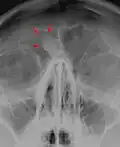

Osteome sind gutartige Knochentumore. Sie besitzen ein langsames Wachstum und bestehen aus einer lokalisierten Neubildung von Knochensubstanz. Am häufigsten entstehen sie im Bereich des Schädels, insbesondere in den Nasennebenhöhlen.

Da sie meist keine Symptome verursachen, werden sie oftmals nur zufällig ab einer gewissen Größenzunahme des Knochens entdeckt. Nachgewiesen werden sie oft im Röntgenbild, wo sie sich schattengebend und scharf begrenzt darstellen. Mit ihrer elfenbeinartigen Farbe heben sie sich oft vom restlichen Knochengewebe ab. Unter dem Mikroskop zeigt sich ausgereiftes und vollständig mineralisiertes Knochengewebe mit in Lamellen angeordneter Schichtung.